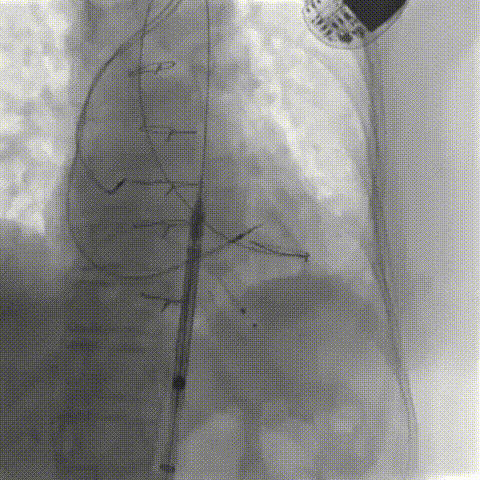

器械过弓柔顺

22mm球囊后扩(1.0倍速播放)